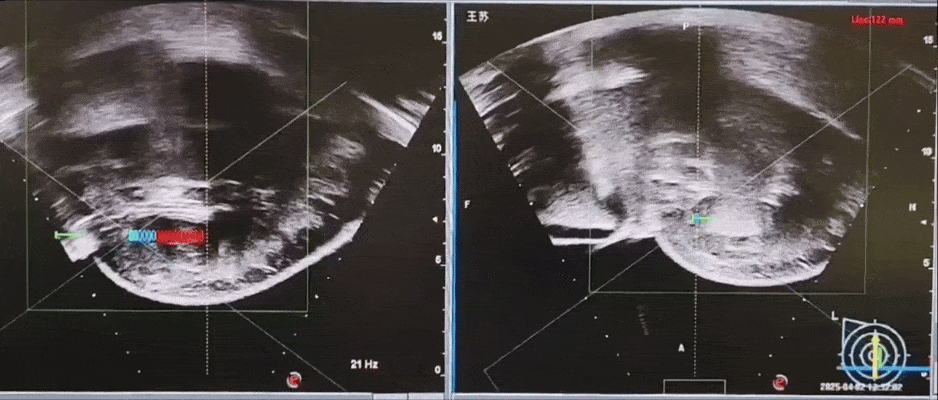

海扶治疗实时超声监控,乳腺肿瘤瞬间“变白”(组织受热变性)

这个“变白”的过程是治疗起效的标志,说明肿瘤已经被成功消融。

整个过程医生都能实时监控,确保治疗精准无误,同时避免伤害到周围的正常组织。

这种可视化的治疗方式,不仅让医生操作更安心,也让患者对治疗效果更有信心。